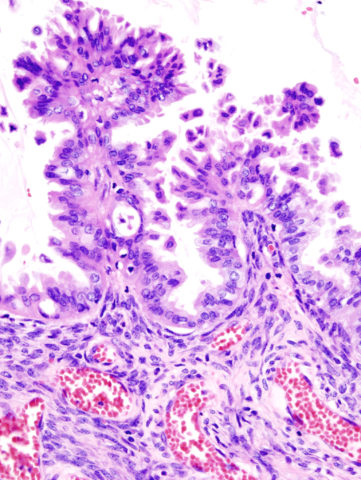

Esistono differenti tipi di carcinoma ovarico, in base al particolare tessuto dell’organo che viene colpito. In linea generale distinguiamo tumori epiteliali (associati all’endometrio, circa il 90% dei casi), stromali (legati ai tessuti che producono ormoni, circa 7% dei casi) e delle cellule germinali (associati agli ovuli, circa il 3% dei casi totali). Esistono numerosi fattori di rischio che possono influenzare il decorso di vita di una paziente, a partire dall’età, visto che la maggior parte dei casi si verifica fra i 50 e i 60 anni. Inoltre, bisogna tenere conto all’atto dell’anamnesi della possibilità di una malattia ereditaria. Esistono infatti delle condizioni tumorali ovariche portate avanti da mutazioni in specifici geni che possono essere ereditate dai genitori. Un gene importante è BRCA1 (ma anche BRCA2), coinvolto anche in forme ereditarie di carcinoma mammario. Altri parametri da tenere in considerazione sono lunghe terapie a base di estrogeni, spesso controindicate in pazienti che presentano lievi anomalie al pap-test o che in generale potrebbero essere suscettibili per altri motivi a trasformazioni neoplastiche della struttura uterina, e la finestra di età fertile. Con questo termine si indica il periodo di tempo fra menarca e ultima mestruazione, prima dell’inizio della menopausa. Avere un menarca troppo precoce o andare in menopausa troppo tardivamente potrebbe essere un fattore di rischio per l’insorgenza di un tumore ovarico.